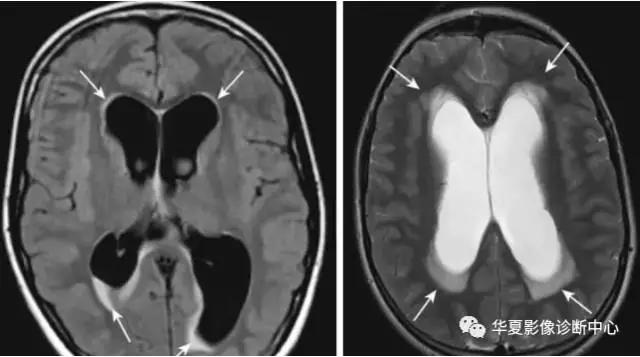

间质性脑水肿

常见于脑积水,多分布侧脑室周围的白质或第三脑室。

主要机制:脑积水造成脑室内压力升高,形成压力梯度,脑脊液透过室管膜进入脑室内的周围的白质。

MR表现:稍长T1,稍高于脑脊液信号,长T2信号,为较高信号。DWI不表现为高信号,ADC常轻度升高。

脑积水患儿,脑室周围条带状边界清楚的低密度灶。